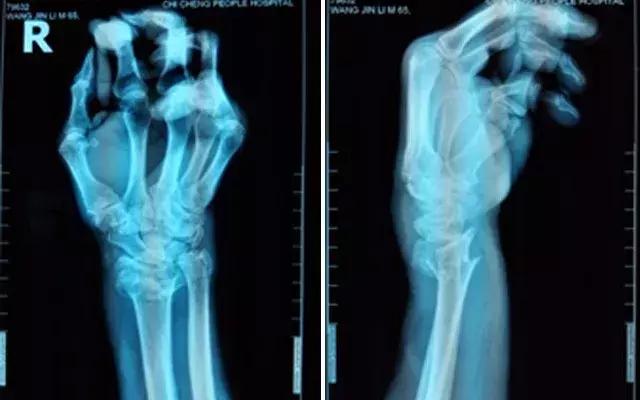

不稳定性骨折就是指骨折端易移位或复位后易再移位者,如斜形骨折、螺旋形骨折、粉碎性骨折、多段骨折、严重的椎体压缩性骨折、合并关节脱位的骨折等。它的特点是:固定后维持复位比较困难,很容易发生再次移位,导致发生畸形愈合。医生会给予患者严格的复位石膏固定,而且需严格按时定期复查,密切观察骨折断端移位情况。如果发生移位,就需要再次复位或手术治疗。常见的如尺桡骨骨折、第一掌骨基底骨折合并腕掌关节脱位等。

张大爷的骨折就属于不稳定的桡骨远端粉碎性骨折,早期虽然复位很好,但是随着患区组织肿胀的减轻,石膏就会出现松动,那么因为骨折端不稳定,复位可能就会出现不同程度的丢失,如果在不可接受范围,而这个时候可能已经错过了手法复位的理想时期,就基本需要手术复位了。